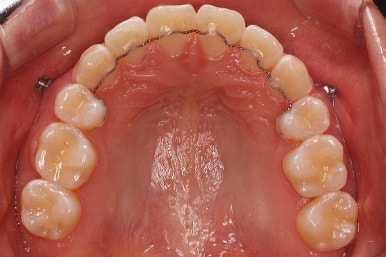

아래턱이 작아서 상대적으로 윗니들이 많이 돌출되었고, 뻐드러져 있습니다. 윗니들이 배열되어 있는 형태도 V자에 가깝게 입천장이 좁은 양상입니다.

장치를 부착하였습니다.

이번에 부착한 장치는 엠파워 클리어라고 하는 자가결찰 세라믹장치 입니다.

세라믹이기 때문에 덜 보이며 자가결찰 장치이기 때문에 초기에 가지런해지는 속도가 빠르고 통증이 덜한 장점이 있습니다.

윗니는 발치를 했고, 잇몸뼈에 미니스크류를 식립하여 앞니를 뒤로 당겨넣고 있습니다.

이 뽑은 자리가 다시 벌어지지 않게 앞니가 다시 틀어지지 않게 유지철사를 부착하고 마무리를 하였습니다.